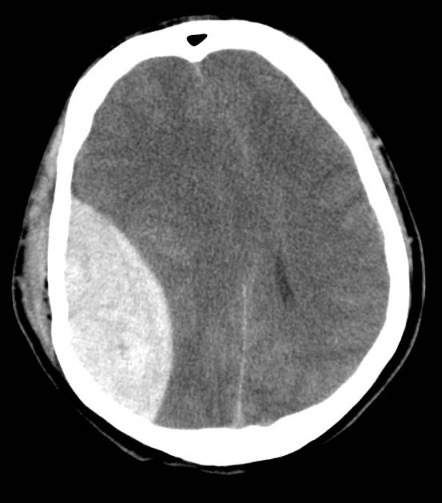

Left subdural with some midline shift

Subdural on CT head

143